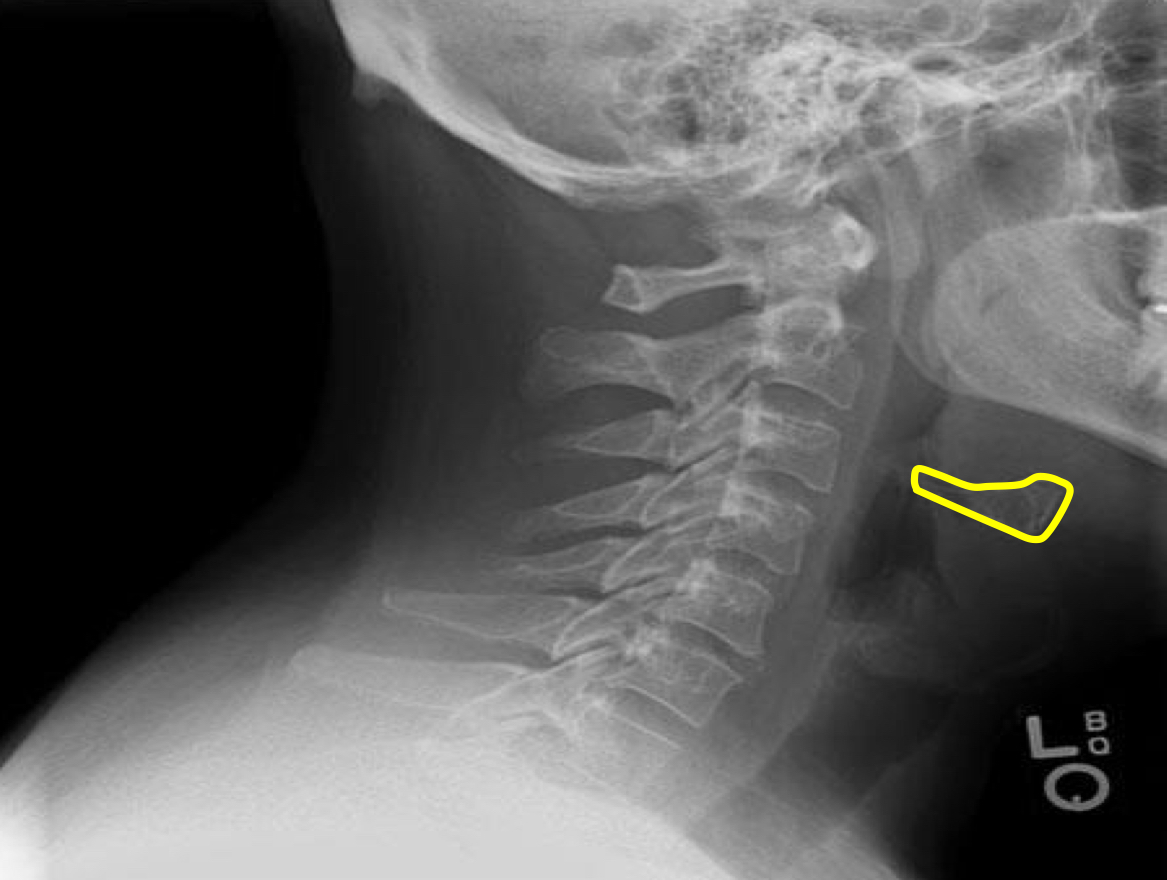

What view is this?

Lateral Cervical

Mandible

Hyoid bone

Mitchel Marker